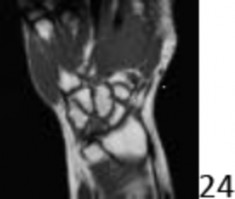

5. # A 38-year-old man reports a 6-month history of pain in his left wrist. He denies any injury and is otherwise healthy. An MRI scan is shown in Figure 24. What is the recommended treatment?

DISCUSSION: The MRI scan shows avascularity (decreased signal intensity on T1-weighted image) of the lunate in an ulnar minus wrist, consistent with Kienbock's disease. No degenerative changes are seen in the carpus. Of the choices listed, radial shortening osteotomy is the treatment of choice. This procedure provides an extra-articular approach to treatment. The other options could be considered in more advanced cases or if joint deterioration/destruction was noted. Lunate excision with tendon interposition and lunate implant arthroplasty are rarely used at this time. An ulnar shortening osteotomy could make the problem worse by increasing the contact forces between the radius and lunate. A limited intercarpal fusion is usually used prior to resorting to total wrist arthrodesis. The Preferred Response to Question # 24 is 1.